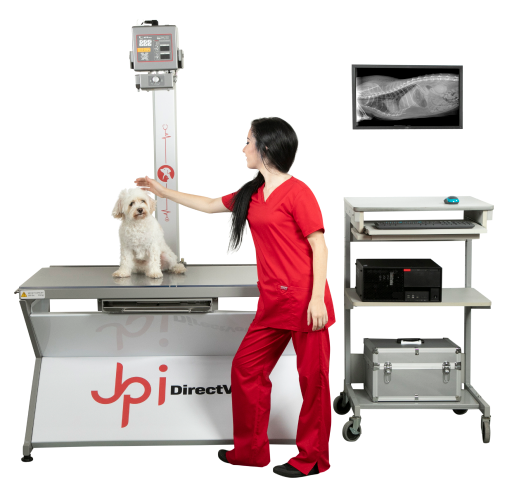

Radiología General y Portatil

¡Estamos cubiertos!

- Radiografías Digitales.

- Espacio reducido – 220 V.

- Sofware ExamVue™ Duo.

- Diseño portátil, liviano y plegable.

- Fácil maniobrabilidad.

- Software ExamVue™ Duo.